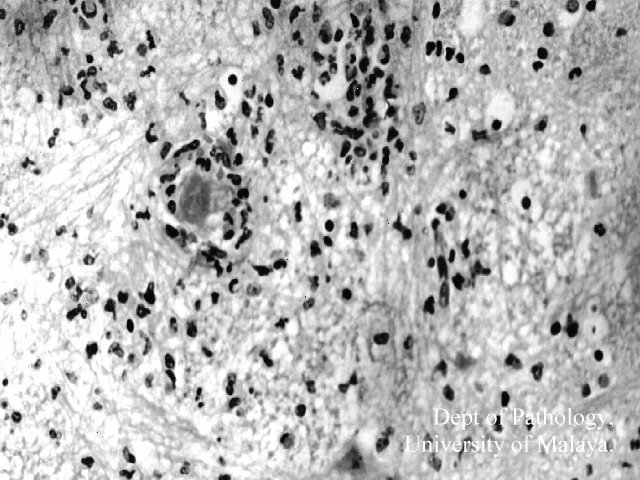

Figure 2: Medulla: Intense inflammation with oedema, microglial nodule formation, and phagocytosis. Some neutrophils are also noted.

Figure 2: Medulla: Intense inflammation with oedema, microglial nodule formation, and phagocytosis. Some neutrophils are also noted. Click on image to see larger picture.

The typical histopathological findings in the brainstem and spinal cord did not differ much from other types of viral encephalitides, and consisted of perivascular inflammation, microglial nodule formation, neuronal necrosis and phagocytosis, and mild meningitis. No neuronal inclusions were detected. The extent of the inflammation was remarkable in that it involved all levels of the spinal cord, medulla, tegmentum of the pons (spares the basis pontis) and much of the midbrain (spares the peduncles). In our cases there was no apparent involvement of the cerebellum, cerebrum or myocardium.